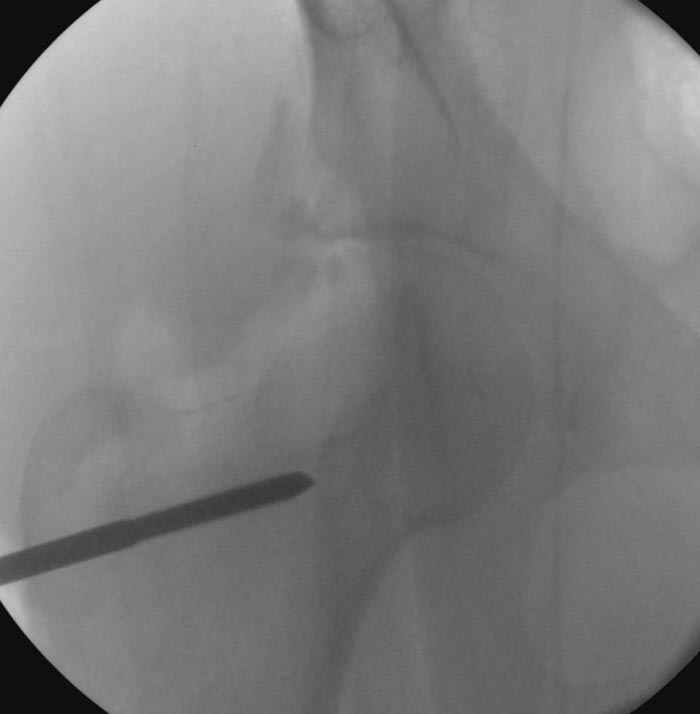

7:30 начало операции, больной на спине, попытка репозиции после анестезии N3, укладка больного на боку, доступ Kocher- Langenbeck, состояние седалищнего нерва около 2.5см кровоподтек, через joistick головка бедра приподнята, освобовождение сустава, фрагмент заднего края более 3х4 см репонирован на свое место. После промывания

сустава, репозиция вывиха (N4), фиксация фрагмента 2.7(4) мм шурупами и допольнительно реконструктивной пластиной на 8 дырок, фиксация 3.5мм шурупами проксимально и дистально.

Интраоперционные N5 косая запирательная и N6 подвздошный снимок